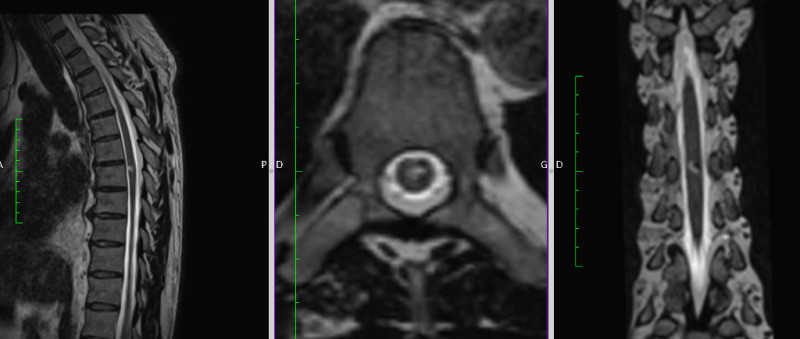

Resonancia Magnética de Columna

Envíado por Dr. José Rafael Chang Calero